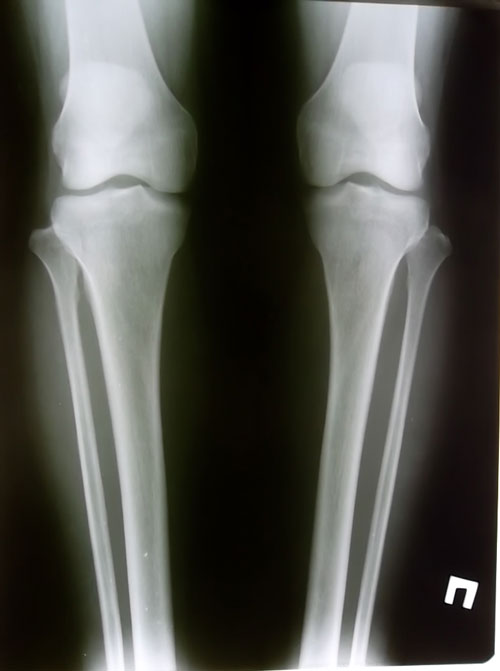

Рентгеновские снимки до операции.

прямая проекция

боковая проекция

рентгеновские снимки после операции, исправление деформации.